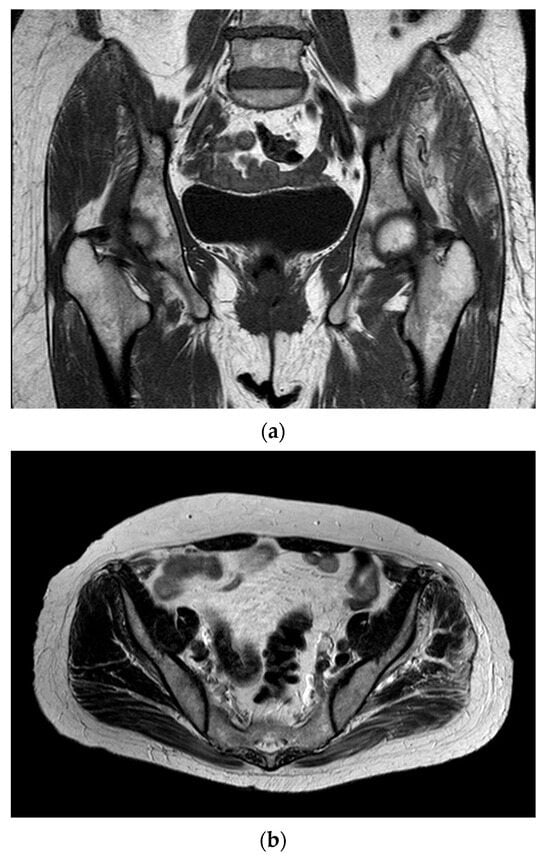

- Pinal-Fernandez, I.; Casal-Dominguez, M.; Carrino, J.A.; Lahouti, A.H.; Basharat, P.; Albayda, J.; Paik, J.J.; Ahlawat, S.; Danoff, S.K.; Lloyd, T.E.; et al. Thigh muscle MRI in immune-mediated necrotising myopathy: Extensive oedema, early muscle damage and role of anti-SRP autoantibodies as a marker of severity. Ann. Rheum. Dis. 2017, 76, 681–687. [Google Scholar] [CrossRef]